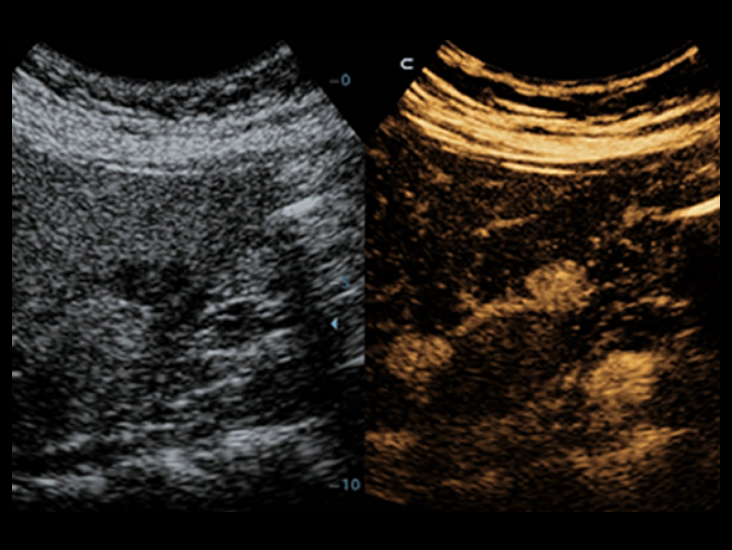

Klasik g?rÞntÞleme teknolojileri: Tan? i?in kalitenin artt?r?lmas?

Yerle?ik ultrason sistemlerinden aktar?lan klasik g?rÞntÞleme teknolojilerinin uygulanmas?yla, Full HD ?zellikli DC-40, g?rÞntÞ ayr?nt?lar?nda size kalite art??? sunar.

- ?Clear (benek azaltma g?rÞntÞleme teknolojisi)

- PSH (Faz Kayd?rma Harmonik g?rÞntÞleme)

- ?Beam: mekansal bile?ik g?rÞntÞleme teknolojisi